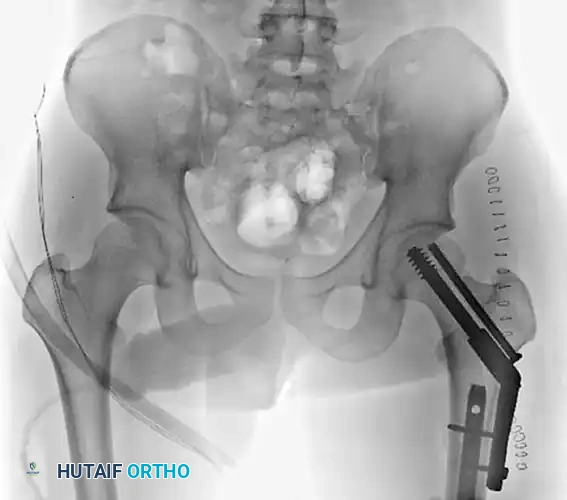

Figure 55-62B: Postoperative radiograph demonstrating fixation of the femoral neck with cannulated screws and the shaft with a retrograde intramedullary nail.

Figure 55-61A: Preoperative radiograph demonstrating a complex Pipkin IV fracture (posterior wall acetabular fracture with an associated femoral head fracture).

Figure 55-61B: Postoperative radiograph following surgical dislocation of the hip, open reduction and internal fixation of the posterior wall acetabular fracture, and débridement of the infrafoveal femoral head fracture.

Figure 55-61E: Postoperative AP pelvic radiograph showing the final construct.